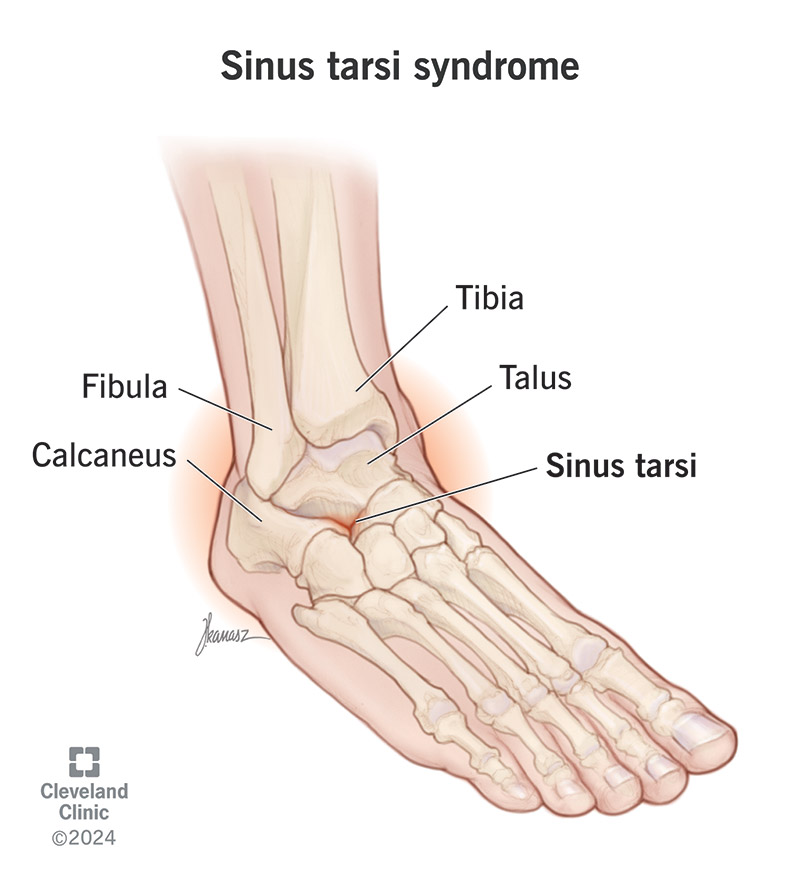

what is the sinus tarsi?

small bony cancel that separates anterior to posterior articulations

when we sprain our ankle, where does the swelling go?

sinus tarsi